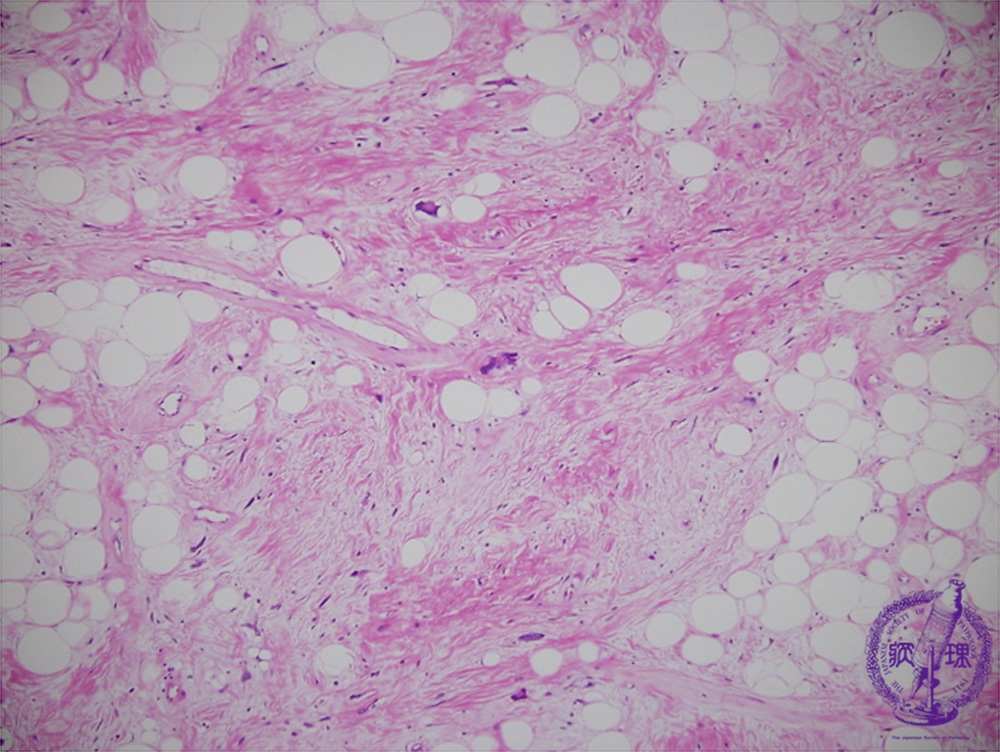

Microscopic findings (H.E. low power view): Hyalinized collagenous connective tissues identified within the fatty tissues.